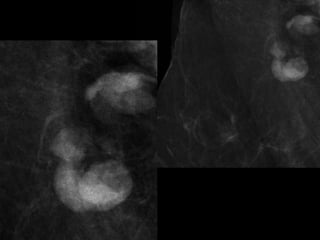

Current Bilateral Mammogram

RCC      LCC             RMLO       LMLO

Current and Comparison Left Breast MGs

4 YRS PRIOR               CURRENT              4 YRS PRIOR

US retroareolar region

US Left upper outer breast

• What are the findings?

• What would you do next?

• What is your differential diagnosis?

• What are your recommendations?